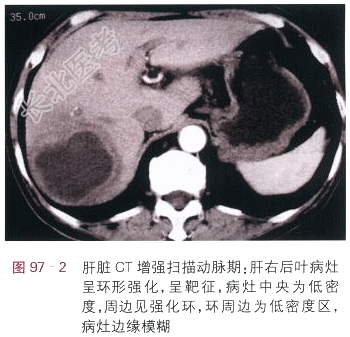

读片分析:肝右后叶包膜下见一低密度团块,呈囊性,内部密度均匀,见一略低密度囊壁,病灶边缘模糊(见图97-1),肝脏CT增强扫描:肝右后叶病灶囊壁呈环形强化,表现为“靶征”,病灶中央为低密度,周边见强化环,环周边为低密度区,病灶边缘模糊(见图97-2~图97-3)。